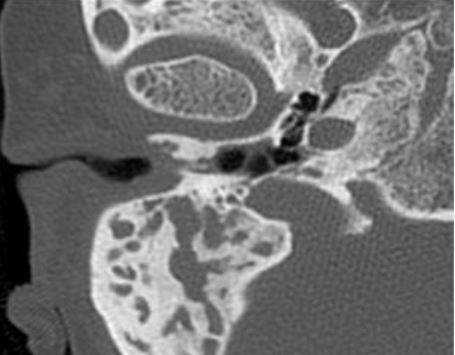

У одного пациента на КТ определялись двусторонняя аномалия внутреннего уха по типу Мондини (рис. 3), двусторонний локальный порок развития цепи слуховых косточек, костная облитерация лабиринта, включая улитку справа. На МРТ внутриулитковая жидкость справа не определялась, слева количество внутриулитковой жидкости было в норме.

Рис. 3. КТ, аксиальная проекция. Аномалия Мондини, состояние после КИ.